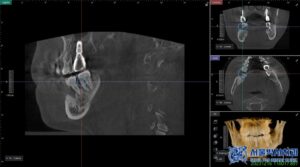

치아를 발치한 후에는

무절개 방식의 임플란트 식립을

진행하기로 하였습니다.

무절개 임플란트는

말 그대로 잇몸을 절개하지 않고

임플란트를 식립하는 방식으로,

컴퓨터 분석을 통해 미리 계산된

정확한 위치와 각도로 위 사진과 같은

수술 가이드를 제작하고,

가이드를 이용해 임플란트를 심기 때문에

수술 부위의 오차를 줄일 수 있습니다.

가이드는 컴퓨터 분석의 정밀한 계산을 통해

고성능 3D프린터로 제작됩니다.